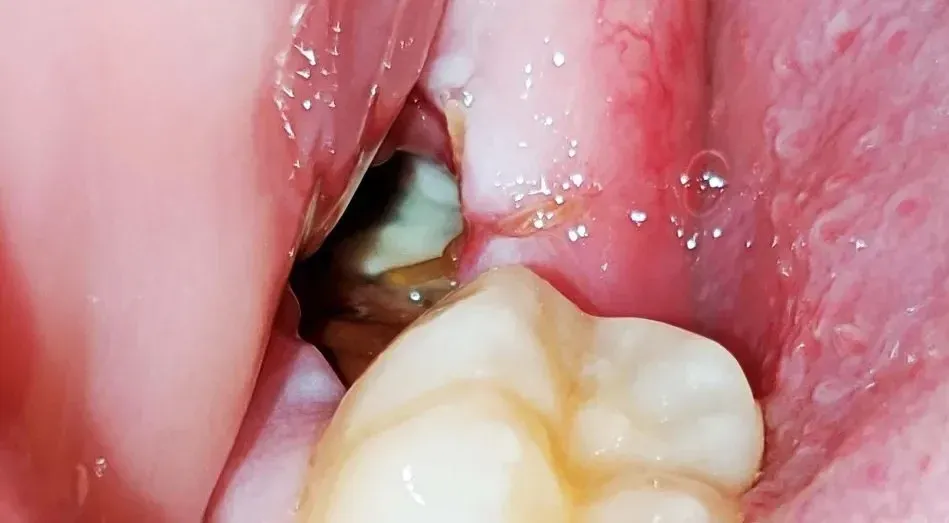

Pictures of dry socket vs normal healing:

After tooth extraction, the healing process might result in either a dry socket or routine healing. The main variations between the two are as follows:

Formation of a blood clot: Following tooth extraction, the exposed bone and nerves in the socket are shielded by a blood clot. The blood clot melts or moves out of the way in a dry socket, exposing the bone and nerves. During average recovery, the blood clot stays in place and serves as a barrier to keep food, germs, and other debris out of the socket.

Manifestation of the socket: During routine healing, the gum tissue will cover it and make it invisible. When there is a dry socket, the gum may appear to have an empty hole.

Visible gum opening: Dry socket results in the blood clot that often develops following a tooth extraction dislodging, exposing the bone and nerves underneath. The vacant socket could be visible to you or feelable to your tongue.